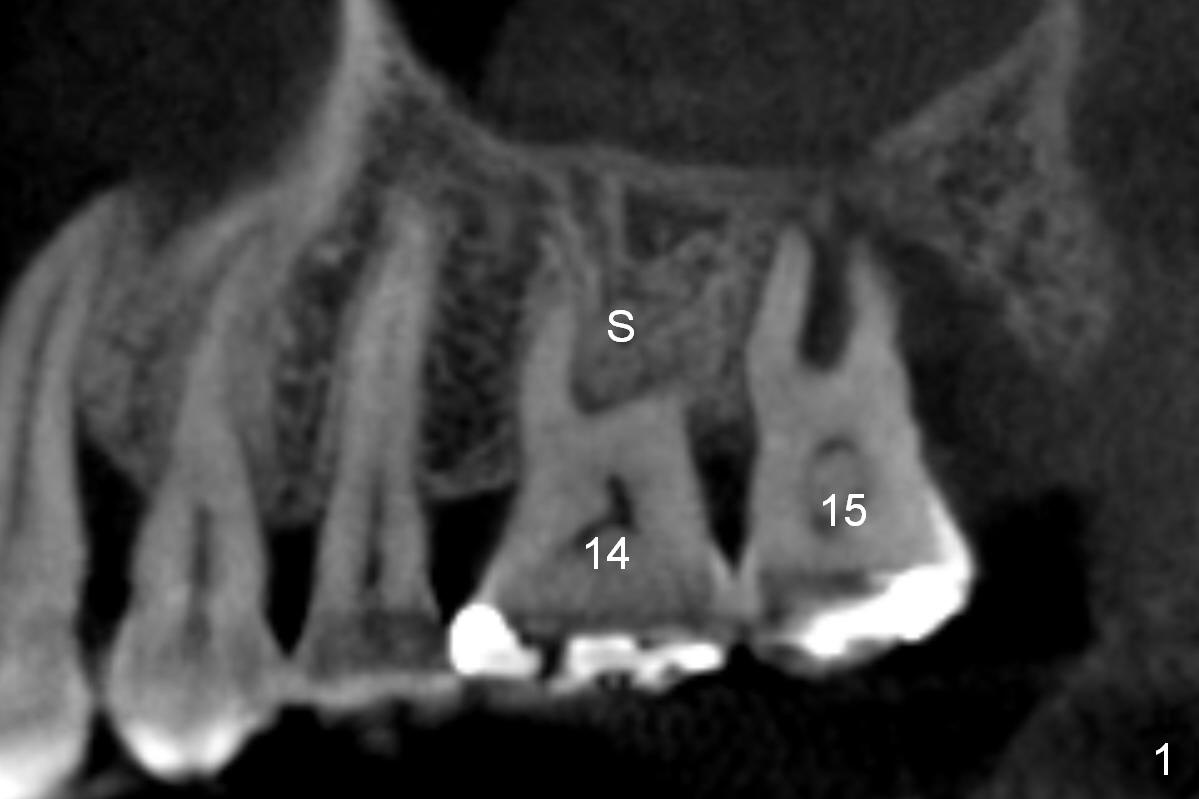

A 48-year-old lady has 4 relative contraindications to immediate implant: 1. infection is so severe at the site of #14 (the posterior maxilla with low bone density, Fig.4,5) that there is no enough bone to support the implant (Fig.7 illustration (1, 2); 2. dental insurance runs out; 3. she shows late in the afternoon when there is not enough staff; 4. she has had 2 immediate implants placed (Fig.4: #15 (3,4)). After socket preservation (Fig.8,9), she is most likely to return for implant placement.

It is noteworthy that the tooth #14 was less affected than #15 22 months earlier (Fig.1 (CBCT sagittal section), 2 (axial), 3 (coronal)). Calculus on the surface of the palatal root (Fig.6 P) is associated with the palatal abscess (Fig.5 P). S: septum.